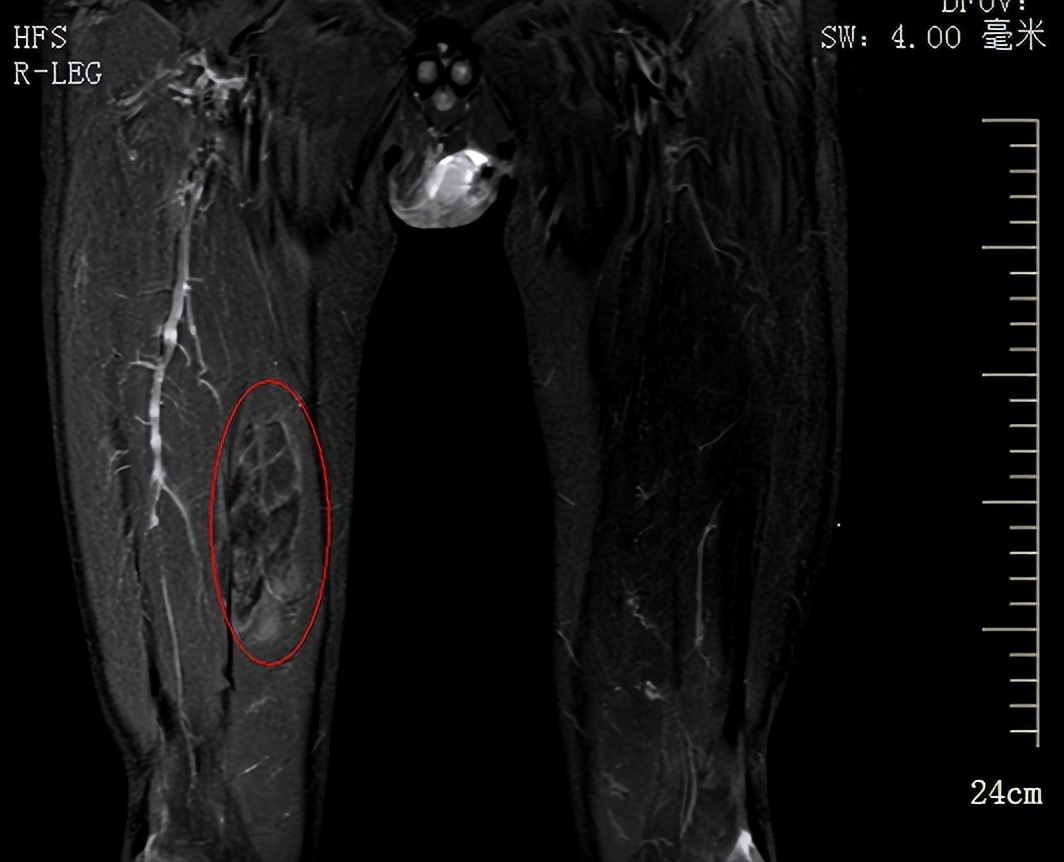

磁共振提示右腿部包块

磁共振示右腿肌内/肌间占位灶